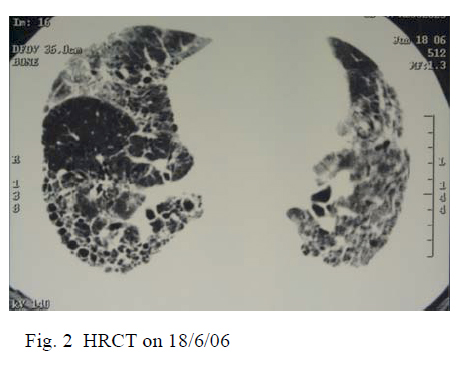

Old chest radiographs in 1999, 2002 and 2004 were traced, showing progressively increased bilateral lower zone reticular shadowing. High resolution computerized tomography (HRCT) of thorax on day 2 of admission showed subpleural fibrosis with honeycombing at bilateral lung bases which was associated traction bronchiectasis. There were ground glass opacities in both lungs and which was predominant in upper zones. There was mild bilateral pleural effusion (Fig. 2).

Histological diagnosis was not made as the patient refused bronchoscopy and surgical lung biopsy. In view of progressive bilateral lower zone reticular shadowing over the past few years, ground glass opacities with underlying usual interstitial pneumonia (UIP) pattern of pulmonary fibrosis on HRCT thorax, and absence of evidence suggesting infections and connective tissue diseases, the clinical diagnosis at that juncture was acute exacerbation of idiopathic pulmonary fibrosis (IPF). The patient was given methylprednisolone 1 g intravenously for 3 consecutive days since day 4 of admission which was then followed by prednisolone 60 mg daily.